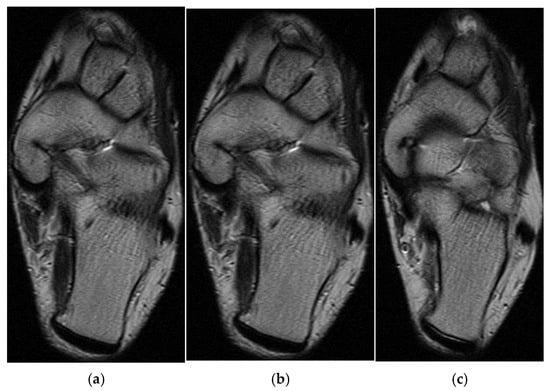

3.3. Case 3: Adductor Complex Strain

In the third case, a left winger reported experiencing sharp pain in the inner left thigh, which severely impaired both active and passive movements during sprints. The left winger, aged 32, has 14 years of experience as a first-league professional in Romania and is a national team member from an urban area, standing 189 cm tall and weighing 90 kg. MRI confirmed the diagnosis of tears and disinsertion of the short adductor tendon and I- and II-degree tears of the obturator externus, pectineus, and adductor longus muscles. STIR sequences show the disinsertion of the short adductor tendon with a gap between the tendon and pubis, with the presence of significant hyperintense alterations, which were also present in the obturator externus, pectineus, and adductor brevis muscles, representing various degrees of fiber tears associated with blood clots (Figure 8).

Figure 8.

(a) Thigh MRI: coronal stir acquisition, (b) thigh MRI: coronal stir acquisition, (c) thigh MRI: axial stir acquisition.

As the reinsertion of the adductor brevis muscle involved an unacceptable period of incapacitation, the adductor magnus, the strongest muscle in the adductor group, being unimpaired, conservative treatment was applied, the player started a physical therapy program focusing on healing first- and second-degree muscle damage, respectively, the hypertonicity and hypertrophy of the other adductor muscles, mainly of the adductor magnus, the strongest muscle in the group. He returned to play after 6 weeks.